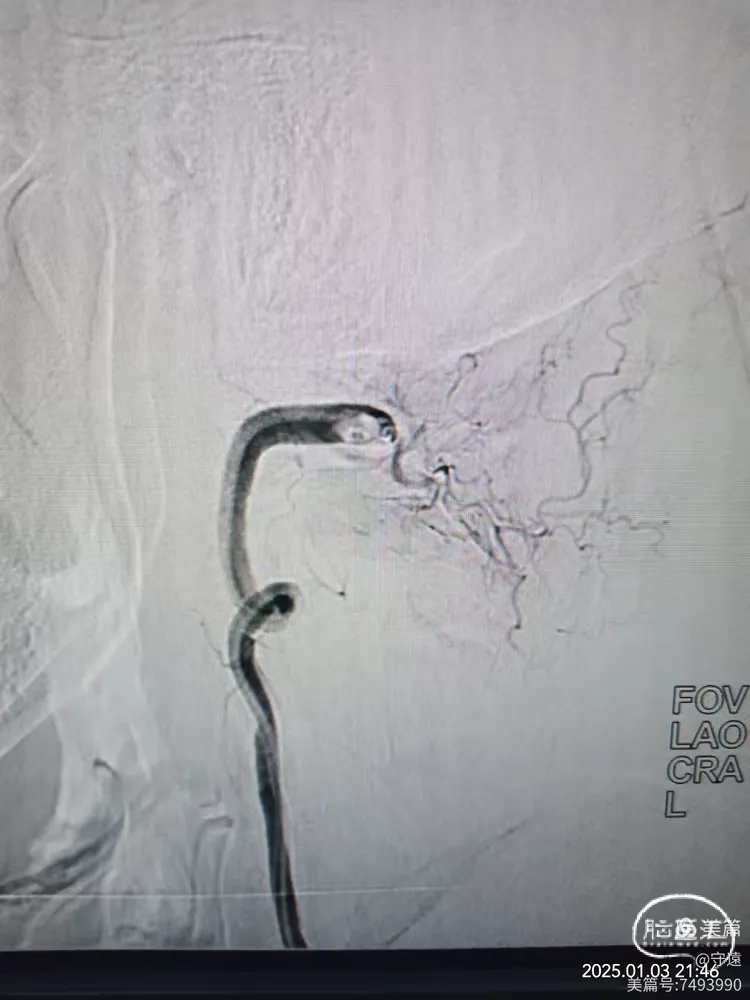

微造影显示:血管再通

回撤导管至V3段造影,狭窄不明显,血流通畅。

回撤至椎动脉起始段造影血流通畅,左侧大脑后似有少量血栓逃逸,推注替罗非班10mL,结束手术。